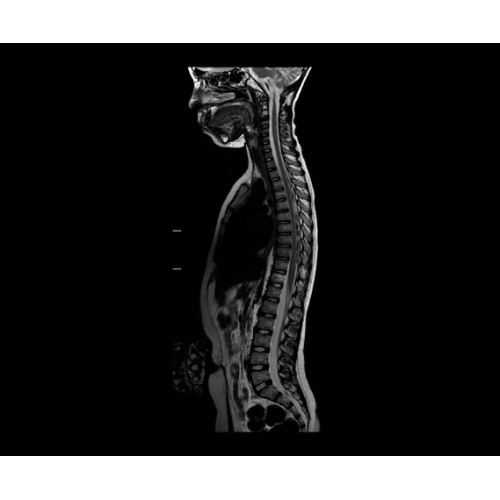

SIGNA PET/MR 3.0T — это гибридная система, в которой совмещаются две принципиально разные технологии — магнитно-резонансную томографию (МРТ) и позитронно-эмиссионную томографию (ПЭТ). Система отличающийся высокой чувствительностью и эффективностью и предназначена для диагностики в области онкологии, неврологии, кардио-васкулярных исследований, исследований воспалительных процессов.

Компания GE Healthcare представляет революционную, полностью интегрированную систему SIGNA PET/MR1, в которой сочетаются времяпролетная технология (TOF) и возможности напряженности магнитного поля 3.0 Тл. Мы поможем вам поднять исследования на более высокий уровень. SIGNA PET/MR позволяет достичь впечатляющей точности и скорости исследований, а благодаря новейшей технологии реконструкции Q.Clear2 качество изображений улучшается в два раза. Кроме того, в систему включен полный набор клинических приложений и гибких катушек для проведения любых видов исследования, открывая для вас возможности визуализации, о которых вы даже не догадывались.

Стандартный пакет приложений SIGNA Works позволит вам достичь желаемых результатов в клинической практике благодаря набору высокоэффективных средств визуализации. Программные приложения, входящие в состав данных клинических пакетов, включают широкий спектр контрастов, функции обработки 2D- и 3D-данных, а также возможность коррекции артефактов движения. SIGNA Works предоставляет набор инструментов, необходимых для проведения эффективного клинического исследования.